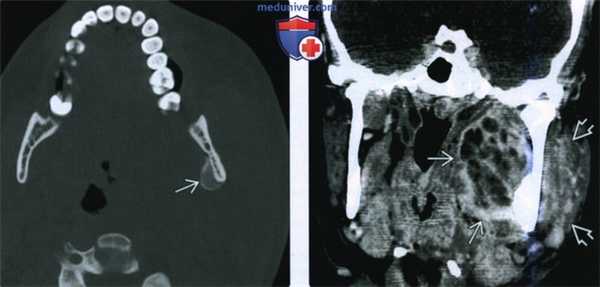

(Слева) На аксиальной КТ с КУ определяется абсцесс внутреннего жевательного пространства слева с вовлечением нижнего края медиальной крыловидной мышцы и воспалением жевательной мышцы. Этот пациент 22 лет с инфекцией моляра, не отвечающей на антибиотикотерапию, предъявляет жалобы на боль, отек и тризм.

(Справа) На аксиальной КТ с КУ у этого же пациента определяется распространение абсцесса книзу в левое поднижнечелюстное пространство. Также наблюдается реактивная лимфаденопатия II уровня.

(Слева) КТ с КУ, аксиальная проекция. Пациентка 22 лет с инфекционным процессом в области нижнего моляра. Антибактериальная терапия неэффективна. Пациентку беспокоят боль, отечность и тризм. При КТ определяется абсцесс левого медиального жевательного пространства, который затрагивает нижнюю часть медиальной крыловидной мышцы. Имеются признаки миозита жевательной мышцы.

(Справа) КТ с КУ, аксиальная проекция, эта же пациентка. Абсцесс распространяется вниз, в поднижнечелюстное пространство. Также имеется реактивная лимфаденопатия лимфоузлов II уровня.